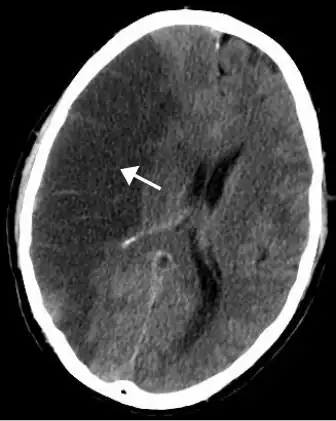

Silent stroke

Silent stroke is stroke that does not have any outward symptoms, and people are typically unaware they had experienced stroke. Despite not causing identifiable symptoms, silent stroke still damages the brain and places the person at increased risk for both transient ischemic attack and major stroke in the future. Conversely, those who have had major stroke are also at risk of having silent stroke.[62] In a broad study in 1998, more than 11 million people were estimated to have experienced stroke in the United States. Approximately 770,000 of these were symptomatic and 11 million were first-ever silent MRI infarcts or hemorrhages. Silent stroke typically causes lesions which are detected via the use of neuroimaging such as MRI. Silent stroke is estimated to occur at five times the rate of symptomatic stroke.[63][64] The risk of silent stroke increases with age, but they may also affect younger adults and children, especially those with acute anemia.[63][65]